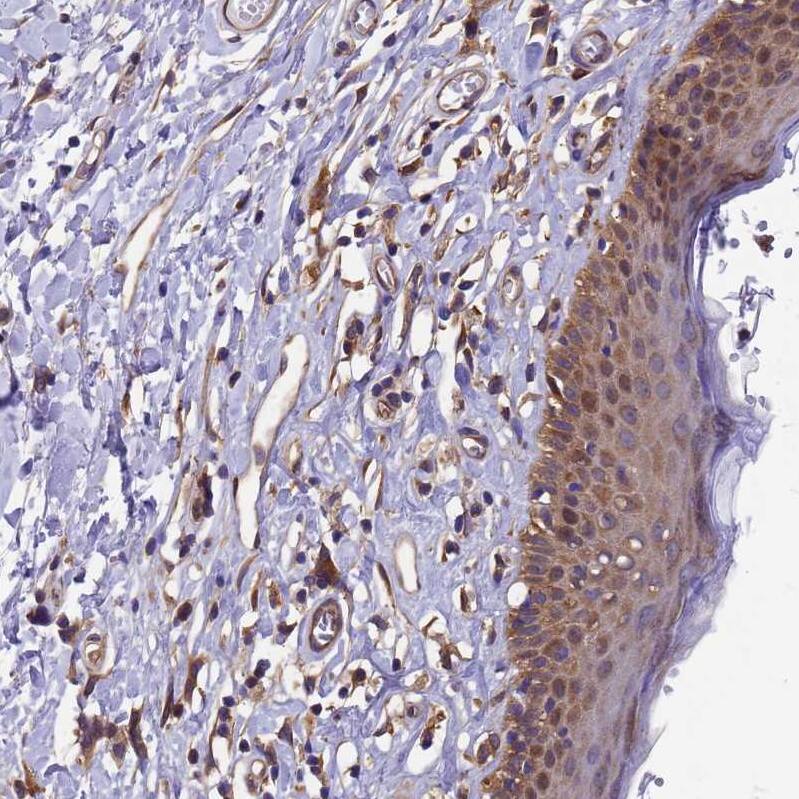

Immunohistochemistry-Paraffin: C17orf39 Antibody [NBP1-91717] -

Immunohistochemistry-Paraffin: C17orf39 Antibody [NBP1-91717] -Staining of human skin shows moderate cytoplasmic/membranous positivity in endothelial cells and squamous epithelial cells.Immunohistochemistry: GID4 Antibody - BSA Free [NBP1-91717]